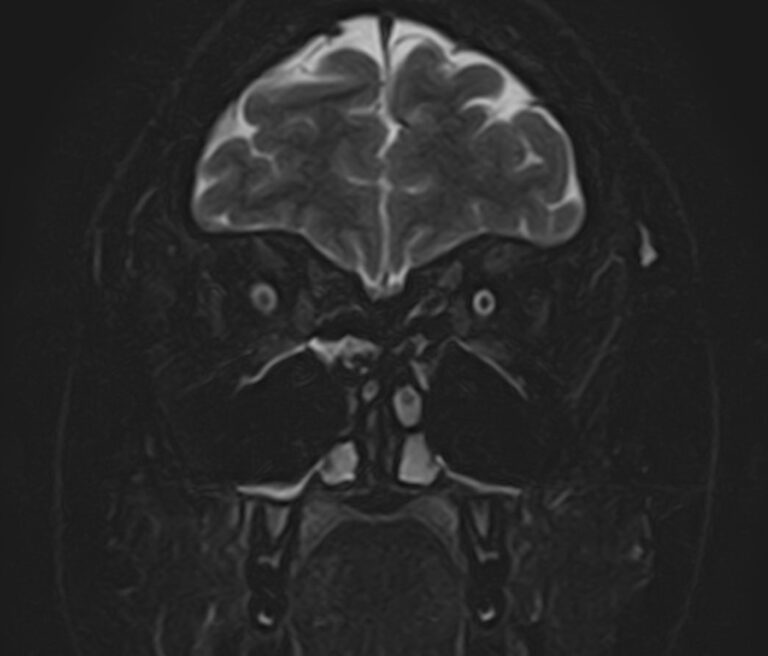

При необходимости визуализации всех отделов головного мозга с прицельным исследованием орбитальной области в клинике «Доступная медицина» проводится комплексное исследование — МРТ головного мозга + МРТ орбит. Это два отдельных исследования, каждое из которых имеет свой протокол сканирования, но при этом они могут проводиться в одно время.

Глазницы (орбиты) — это углубления в лицевом черепе, в которых расположены глазные яблоки, жировая клетчатка, мышцы глаза со связочным аппаратом, слезные железы, зрительные нервы. Волокна зрительных нервов проходят через анатомические отверстия глазниц в полость черепа, затем после частичного перекреста направляются к подкорковым зрительным анализаторам, а от них нервные окончания идут к зрительным центрам коры головного мозга в затылочной области.

Зрительный путь достаточно длинный и на всем его протяжении могут возникнуть патологические процессы, которые становятся причиной нарушения зрения. Иногда это связано с патологией другой области головного мозга, например, опухолью гипофиза. Поэтому в ряде случаев необходимо провести одновременное сканирование глазных орбит и головного мозга, чтобы выяснить, на каком отрезке пути произошло поражение, которое привело к снижению зрения.

Что покажет МРТ головного мозга + МРТ орбит

При обследовании головного мозга и орбит можно выявить:

• Опухоли орбит, воспалительные изменения глазного яблока и его придатков.

• Атрофию зрительного нерва, отслойку сетчатки, инородные тела орбитальной области.

• Объемные образования головного мозга или гематомы, сдавливающие зрительные пути.

• Очаги ишемического инсульта, кровоизлияние после геморрагического инсульта в подкорковых структурах, где расположены зрительные анализаторы, либо в затылочных долях, где находится зрительная кора головного мозга.